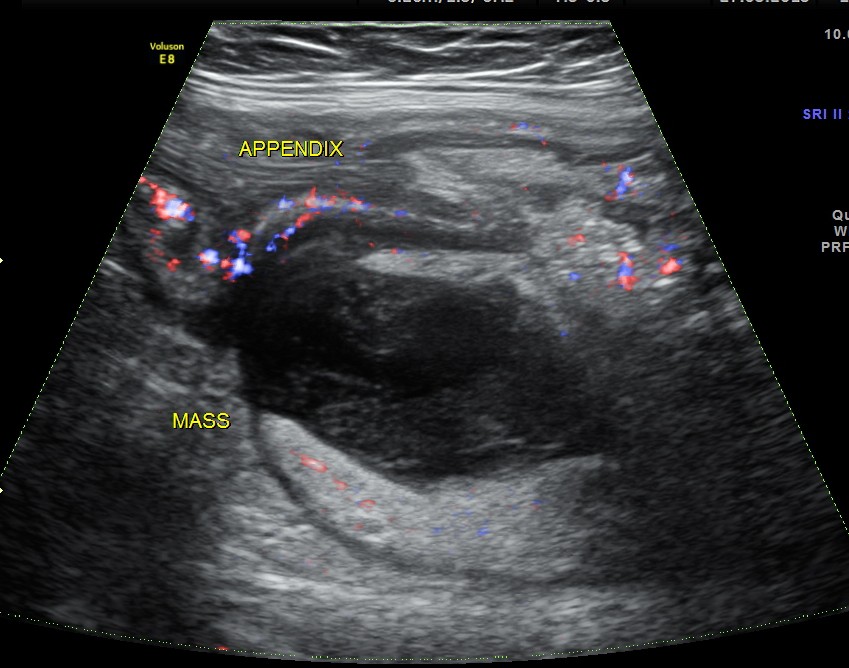

The RIF showed the inflamed appendix communicating with an appendicular mass beneath it.

The following shows the colour Doppler findings.